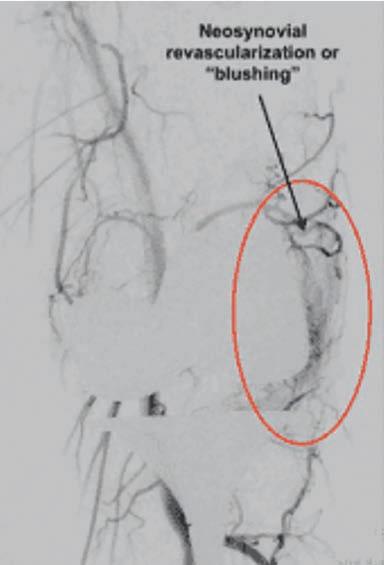

“Lipid metabolism is complex, and the lipid content of plaque is not only cholesterol,” Professor Hamzah elaborated.

“Once you have advanced disease, it’s already too late because lipids have accumulated in the arterial wall, and they are now complex lipids converted into esters from circulating lipids. They mix with glycogen, glycerol, and other compounds before being converted into solid crystals, for example.

“What is clear is that there is currently no drug that breaks down lipids once they are taken up by the cells, and there is no agent that can target lipids in the vessel wall specifically.”

Even though researchers have tried to target plaque previously, none have succeeded, she said, a factor that might be, in part, due to their lack of specificity to the foam cells in the plaque.

“We have patented a drug, developed here at the Harry Perkins Institute that is a reconstructed fusion protein, two proteins joined together, consisting of a biologic agent and ligand that has specific recognition to a receptor that is aberrantly expressed in lipidenriched cells (foam cells) in the arterial wall.

“Hence, this agent, once it enters the blood circulation, targets and accumulates in the arterial wall where lipid deposits and plaques are located.

“That chemical sensor is the key to targeting this drug effectively. It accumulates very well with an excellent biodistribution profile in plaque relative to normal healthy tissue. It congregates on those areas where it is needs to be, and that is exactly what we engineered it to do.

“We know by looking at Professor Jansen’s patient samples from surgery where patients have had plaques removed from their carotid arteries to prevent stroke, all of them seem to show recognition of this drug in lipid-rich regions.

“The original protein is actually naturally produced in our body. When we have a disease, this protein is produced in a high amount and acts on multiple cell types. We reprogram it differently to produce an exclusive effect on lipid-loaded cells, without toxicity. “Its action is highly reproducible throughout the entire arterial system, including the small vessels, and we now know how our drug triggers the cell to metabolise the lipids.”

Professor Hamzah explained that because this novel treatment works by breaking down the chemistry of the lipid itself, using its own processes to do so, the drug effect is specific to plaques.

“We have measured biomarkers for systemic toxicity, we've looked at changes in the arterial wall, blood pressure, etc. When we looked at the baseline clinical markers that we measure in patients who have problems with toxicity and also in a cardiovascular event (such as

creatinine kinase, Mvc2, and uric acid), we could see that the levels were the same as those for the healthy control group.”

The drug is currently undergoing regulatory requirements for approval and commercialisation, but once it is ready for release, both women believe that it could revolutionise treatment for PAD globally.

“Of course, the ideal scenario would be for humans not to get PAD in the first place. However, for those patients who progress despite risk factor management and healthy living, this drug could be an option,” Professor Jansen said.

“There's no reason to think that this could not be a GP prescribed drug, though it will definitely be in the domain of specialists to begin with.”

“The challenging part of bringing a new drug to market is convincing funding bodies that you have a strong contender,” Professor Hamzah explained.

“Even though this is a potential blockbuster, it was tough to convince ourselves and then other people that it was possible to safely and effectively dissolve atherosclerotic plaques. It took us 10 years to replicate the pre-clinical studies that work each time. Only now, I feel more convinced that it's not a fluke or chance.

“It's not completely 100% guaranteed, but it's a ‘first in class’ situation, there is nothing else to compare it with.

“We still have challenges ahead with the human protein – such as, how conserved is the effect of the drug in a human? So that’s our focus now.”

“All the medical management and procedures we have for PAD and CLTI are good, but they are not curative,” Prof. Jansen concluded. “We're thinking about applying the word cure to a pathology that has never had the concept applied to it. And, if it continues to prove itself, that will mean a dramatic difference to millions of people.”